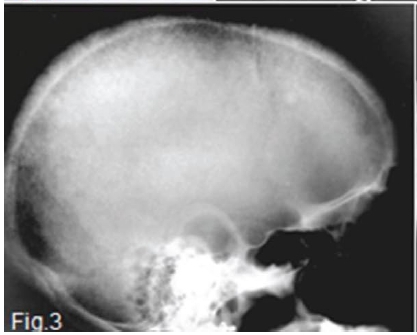

A diagnosis of secondary hyperparathyroidism was made. Her blood picture at the time was as follows: serum calcium within normal limits, urea increased 7-fold, creatinine 13-fold and alkaline phosphatase 7-fold. The pantomograph (Fig. 2) shows generalized relative rarefaction of the jawbones and absence of the lamina dura around the teeth giving the roots a tapered appearance. A unilocular radiolucency (red arrow) is discernible distal to the lower left 2nd molar tooth in the mandible, suggestive of a brown tumour. The skull radiograph (Fig. 3) shows a generalized granular appearance. The radiopaque outlines of the maxillary sinus are not discernible. (Figs 2 and 3). Figure 4 shows granularity of trabecular pattern in bones of the hand and wrist and subperiosteal erosion of the cortex (green arrow), especially in the mid phalanges, and erosion of the terminal tufts (yellow arrow).A biopsy specimen was taken from the mandibular radiolucent area. Microscopic examination revealed a cellular fibrous lesion containing irregular trabecular bone and a few scattered multinucleated giant cells. With the available clinical data a diagnosis of a brown tumour of secondary hyperparathyroidism was made.